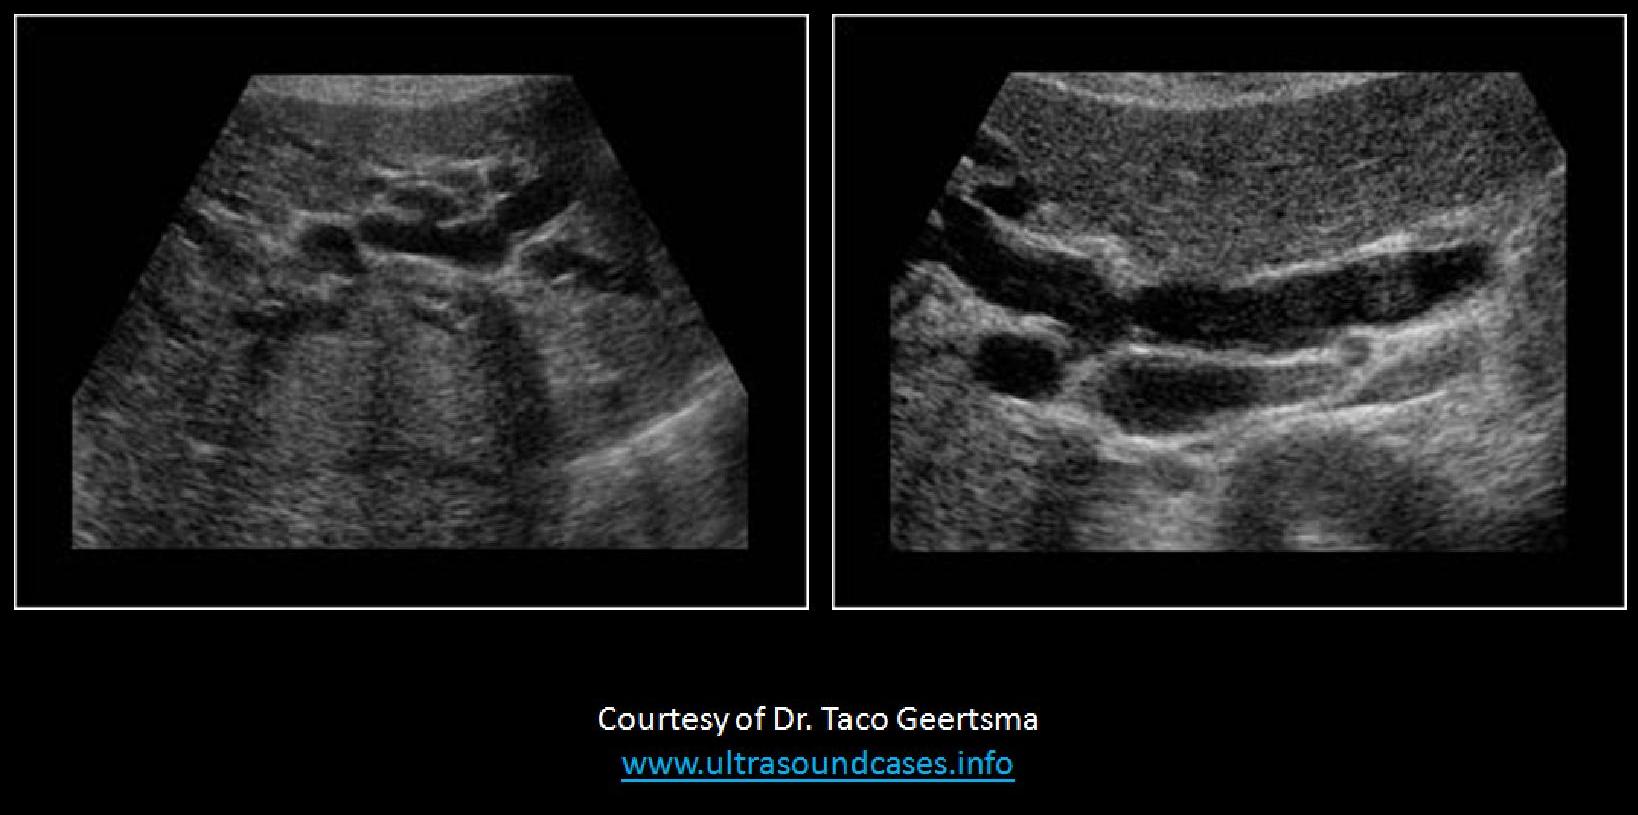

Which of the following statements correctly, describes the findings on the image?

The portal vein is measured correctly and demonstrates possible portal hypertension